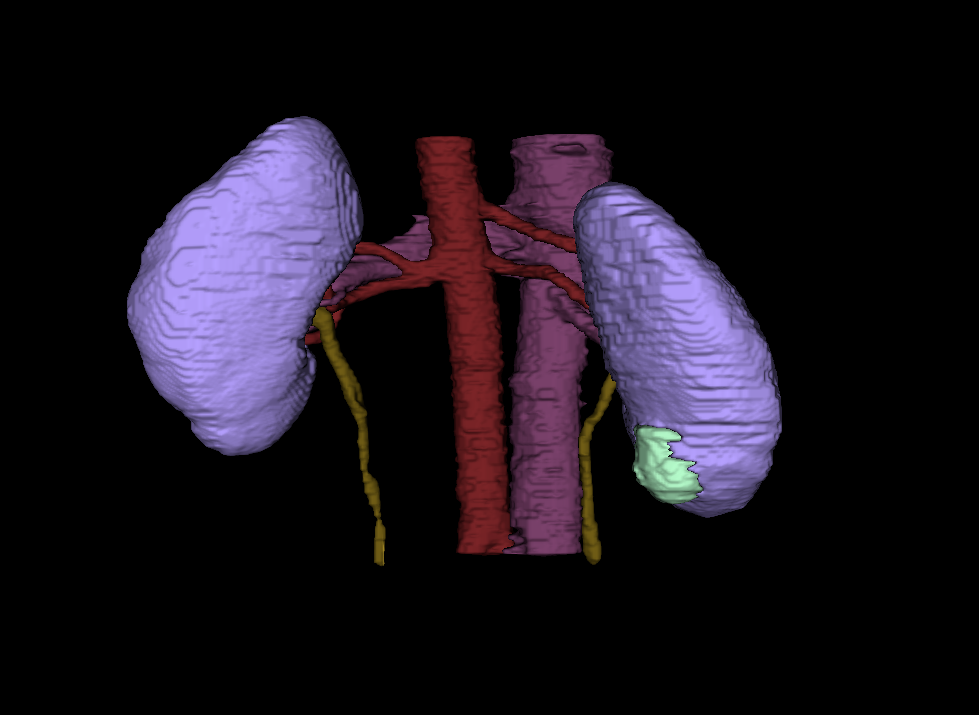

Enhanced Imaging Could Provide Quicker, More Precise Diagnosis for Malignant Kidney Tumors

With a click of a button, ARCS Scholar Nick Heller is helping radiologists identify and analyze kidney tumors within a patient’s body.

Heller is a PhD student conducting computer science research at University of Minnesota. His research focuses on using computer technology to enhance medical imaging, like a CT scan or an MRI. According to Heller, the magnified images will allow radiologists to quantify the type of tumor it is, saving time between a patient’s diagnoses and treatment.

“They will be able to measure a tumor mass, determine how big and rough they are, and whether they look distinct or blurry against the background. Medical professionals can use that information to choose the most effective treatment and predict a patient's outcome,” Heller explains.

(Courtesy: Nick Heller)